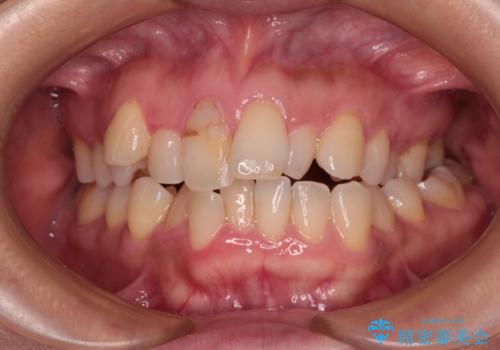

銀歯を白くしたい 一緒に矯正治療も行ない美しい口腔内に